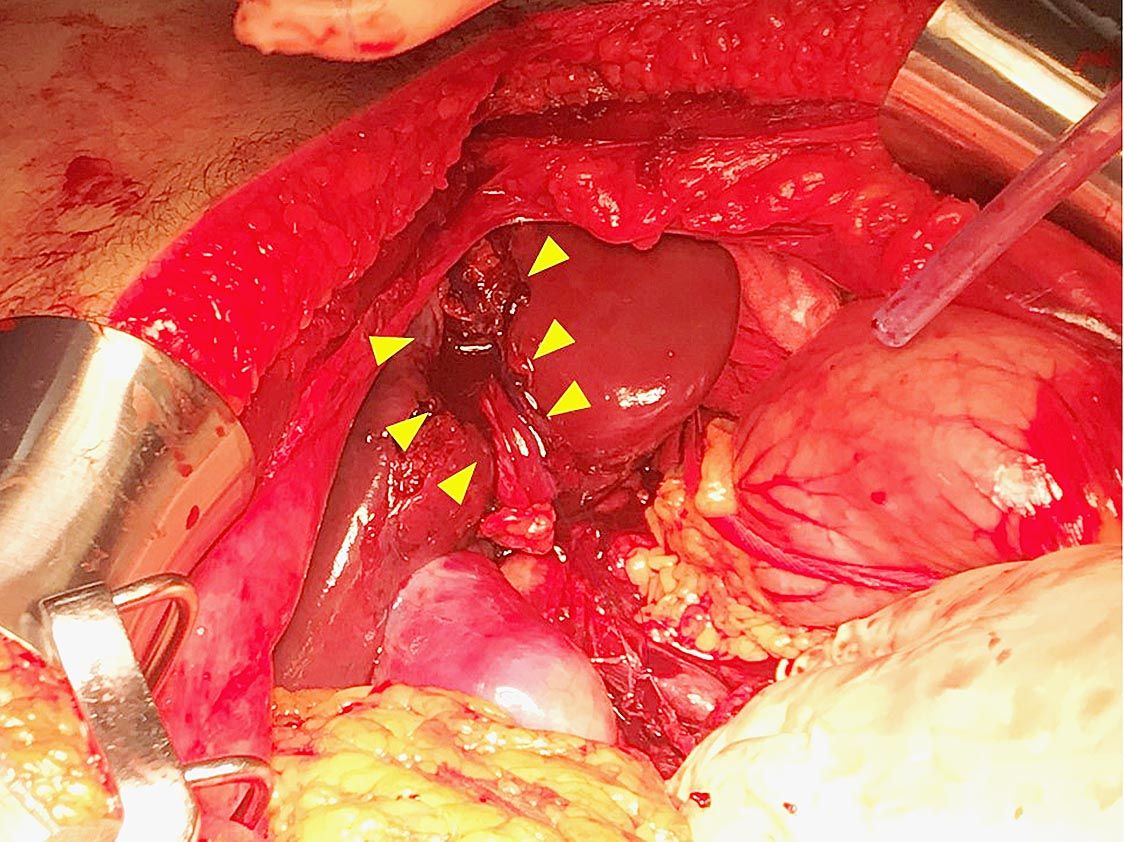

〇実質臓器損傷とは 実質臓器とは中身の詰まった臓器であり、中が空洞の管腔臓器と対をなす。具体的には肝臓、脾臓、腎臓、膵臓が腹部実質臓器である。 肝臓は右横隔膜下にあり栄養の貯蓄や合成、有害物質分解、胆汁生成など様々な機能を持つ。脾臓は左横...